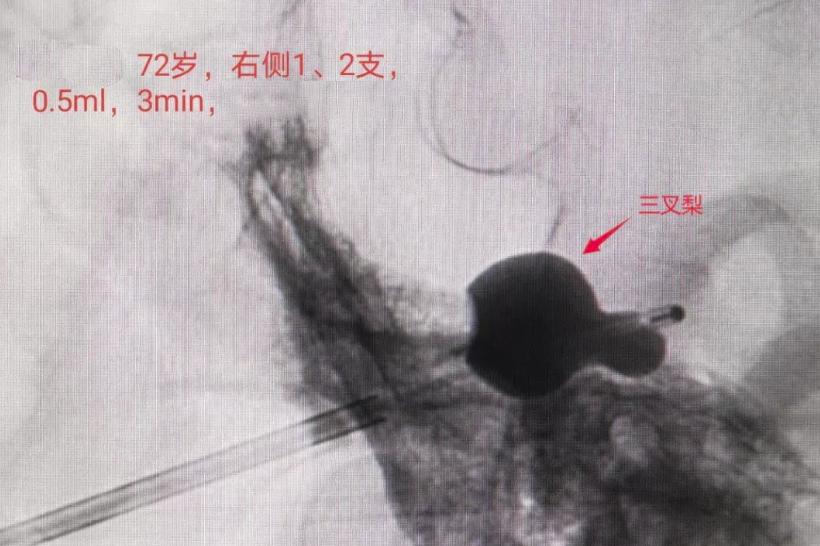

经过综合评估王大爷的病情状况后、决定以“介入三叉神经半月节微球囊压迫术”为他进行手术治疗。手术仅花费15分钟便完成,且术后疼痛症状立刻得到缓解,术后3天王大爷就康复出院。

这个球囊可大有来历,这个运用球囊的手术其实是一种无痛的微创治疗,是三叉神经痛的一种治疗方法,叫“介入三叉神经半月节微球囊压迫术”。